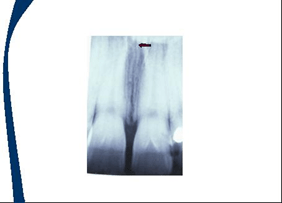

En las imagenes aparecen flechas que representan la localización de los landmarks o puntos de referencia

Sombra de la nariz

Sombra del labio